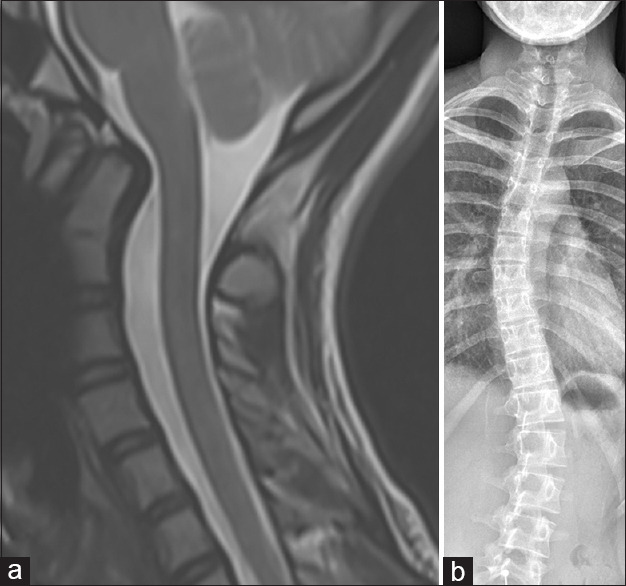

Objective: The odontoid process is an important anatomical structure providing a balance of mobility and stability at the craniocervical junction, with structural and biomechanical associations, and morphology that can be quantified with various measurements. The odontoid tilt angle is a measurement that must be accurately performed and can guide further investigations.

Materials and methods: Retrospective analysis of 100 cervical spinal magnetic resonance imaging was performed on patients investigated for neck pain, with a known history of scoliosis, and compared with 50 control patients. Posterior odontoid tilt and Cobb angles were measured by a musculoskeletal radiology fellow and a fellowship-trained musculoskeletal radiologist with more than 10 years of experience, with descriptive statistics then performed on the measurements.

Results: One hundred and thirty-two patients met the inclusion criteria, across both the scoliosis and control groups. 9 (18%) patients from the control group demonstrated posterior odontoid tilt, compared with 35 (43%) of patients in the scoliosis group. A range of scoliosis curve morphologies were demonstrated: 62 thoracolumbar, 10 thoracic, 9 lumbar, and 1 cervicothoracic, with average Cobb angles of 24.3°, 26.9°, 23.4, and 54°, respectively. There was good interobserver agreement for both measurements and a statistically significant difference in the posterior odontoid tilt measurements between groups (99% confidence interval, P = 0.0064).

Conclusion: We recommend opportunistically assessing for the posterior odontoid tilt (Leaning odontoid tower of BRUMES (Botchu; Raja Rasul; Uldin; Morgan;Elias; Sonal, Shashank, Shirodkar). In cases with a posterior tilt angle >5°, we recommend whole spine imaging to assess for scoliosis in the thoracolumbar spine.